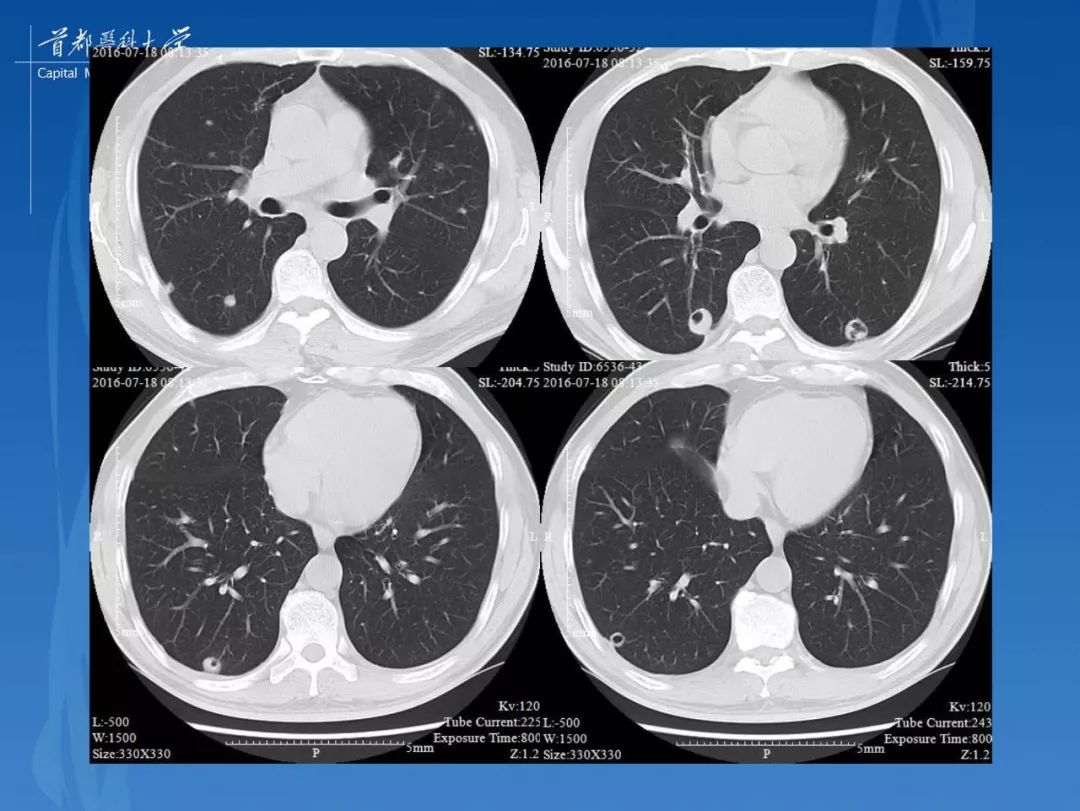

变态反应性肉芽肿性血管炎(css) 肺ct肺窗

图片尺寸1258x1191